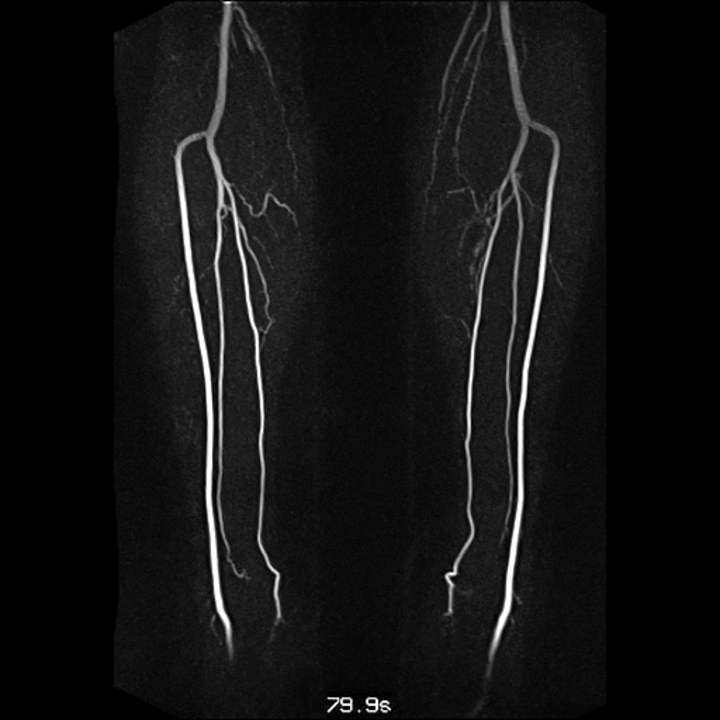

Home Anatomy Lower Limb Angiography 9 years ago 9 years ago Anatomy, Cardiology, Radiology Lower Limb Angiography by samer176 9 years ago9 years ago 131views [zombify_post] Post PaginationPrevious PostPreviousNext PostNext angiogram, gif, Lower limb angiography